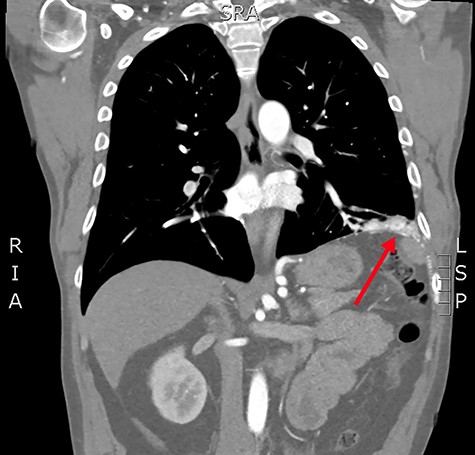

Axial slice from the CTPA, demonstrating the large, complex PAVM in the left lung’s lower lobe (red arrow).

Concerned for pulmonary embolism (PE), a computed tomography pulmonary angiogram (CTPA) was arranged. PE was excluded; however, it did reveal a complex left-sided intra- and extrathoracic vascular malformation within the anteromedial segment of the left lung’s lower lobe, the lingula segment, the subdiaphragmatic space and the left chest-wall (Figs. 1 and 2). The arterial supply derived from large tortuous vessels arising from a combination of the coeliac trunk, six posterior intercostal arteries and the left inferior phrenic artery (Fig. 3). It then communicated with the left upper and lower lobe subsegmental pulmonary arteries, and the left lower lobe pulmonary vein. Subsequent echocardiography was normal, with no significant valvular pathology—evidencing that the pansystolic murmur was an arteriovenous bruit.